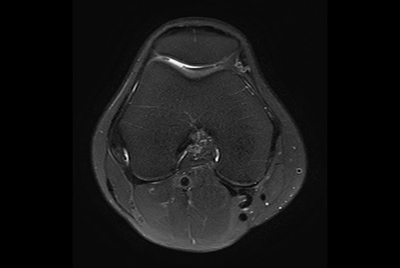

SmartSpeed Traumatic Knee imaging

SmartSpeed 2 min Knee imaging

High quality Knee imaging in short scan times

Knee imaging with Compressed SENSE

Knee exam with/without Compressed SENSE